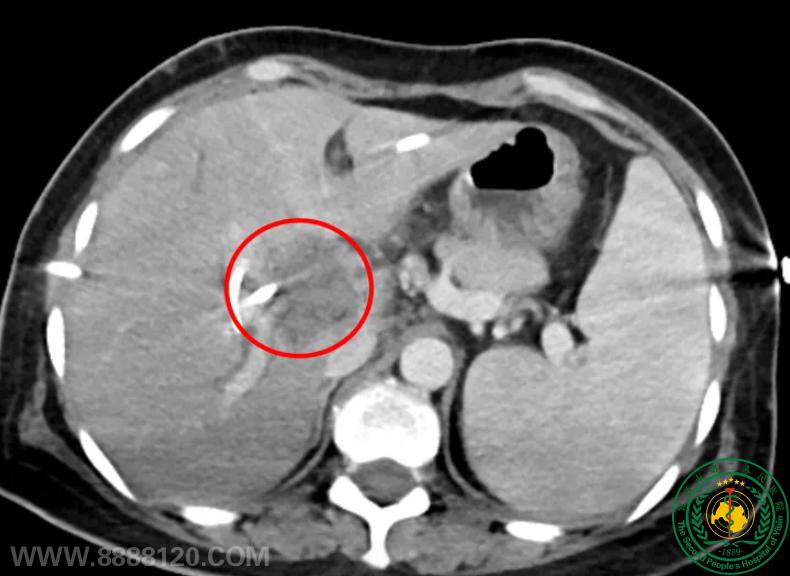

突破生命禁区!我院介入科成功完成川南首例、四川地市级医院首例经皮肝肿瘤纳米刀消融术,为肝门部恶性肿瘤患者带来新希望

突破生命禁区!我院介入科成功完成川南首例、四川地市级医院首例经皮肝肿瘤纳米刀消融术,为肝门部恶性肿瘤患者带来新希望62550